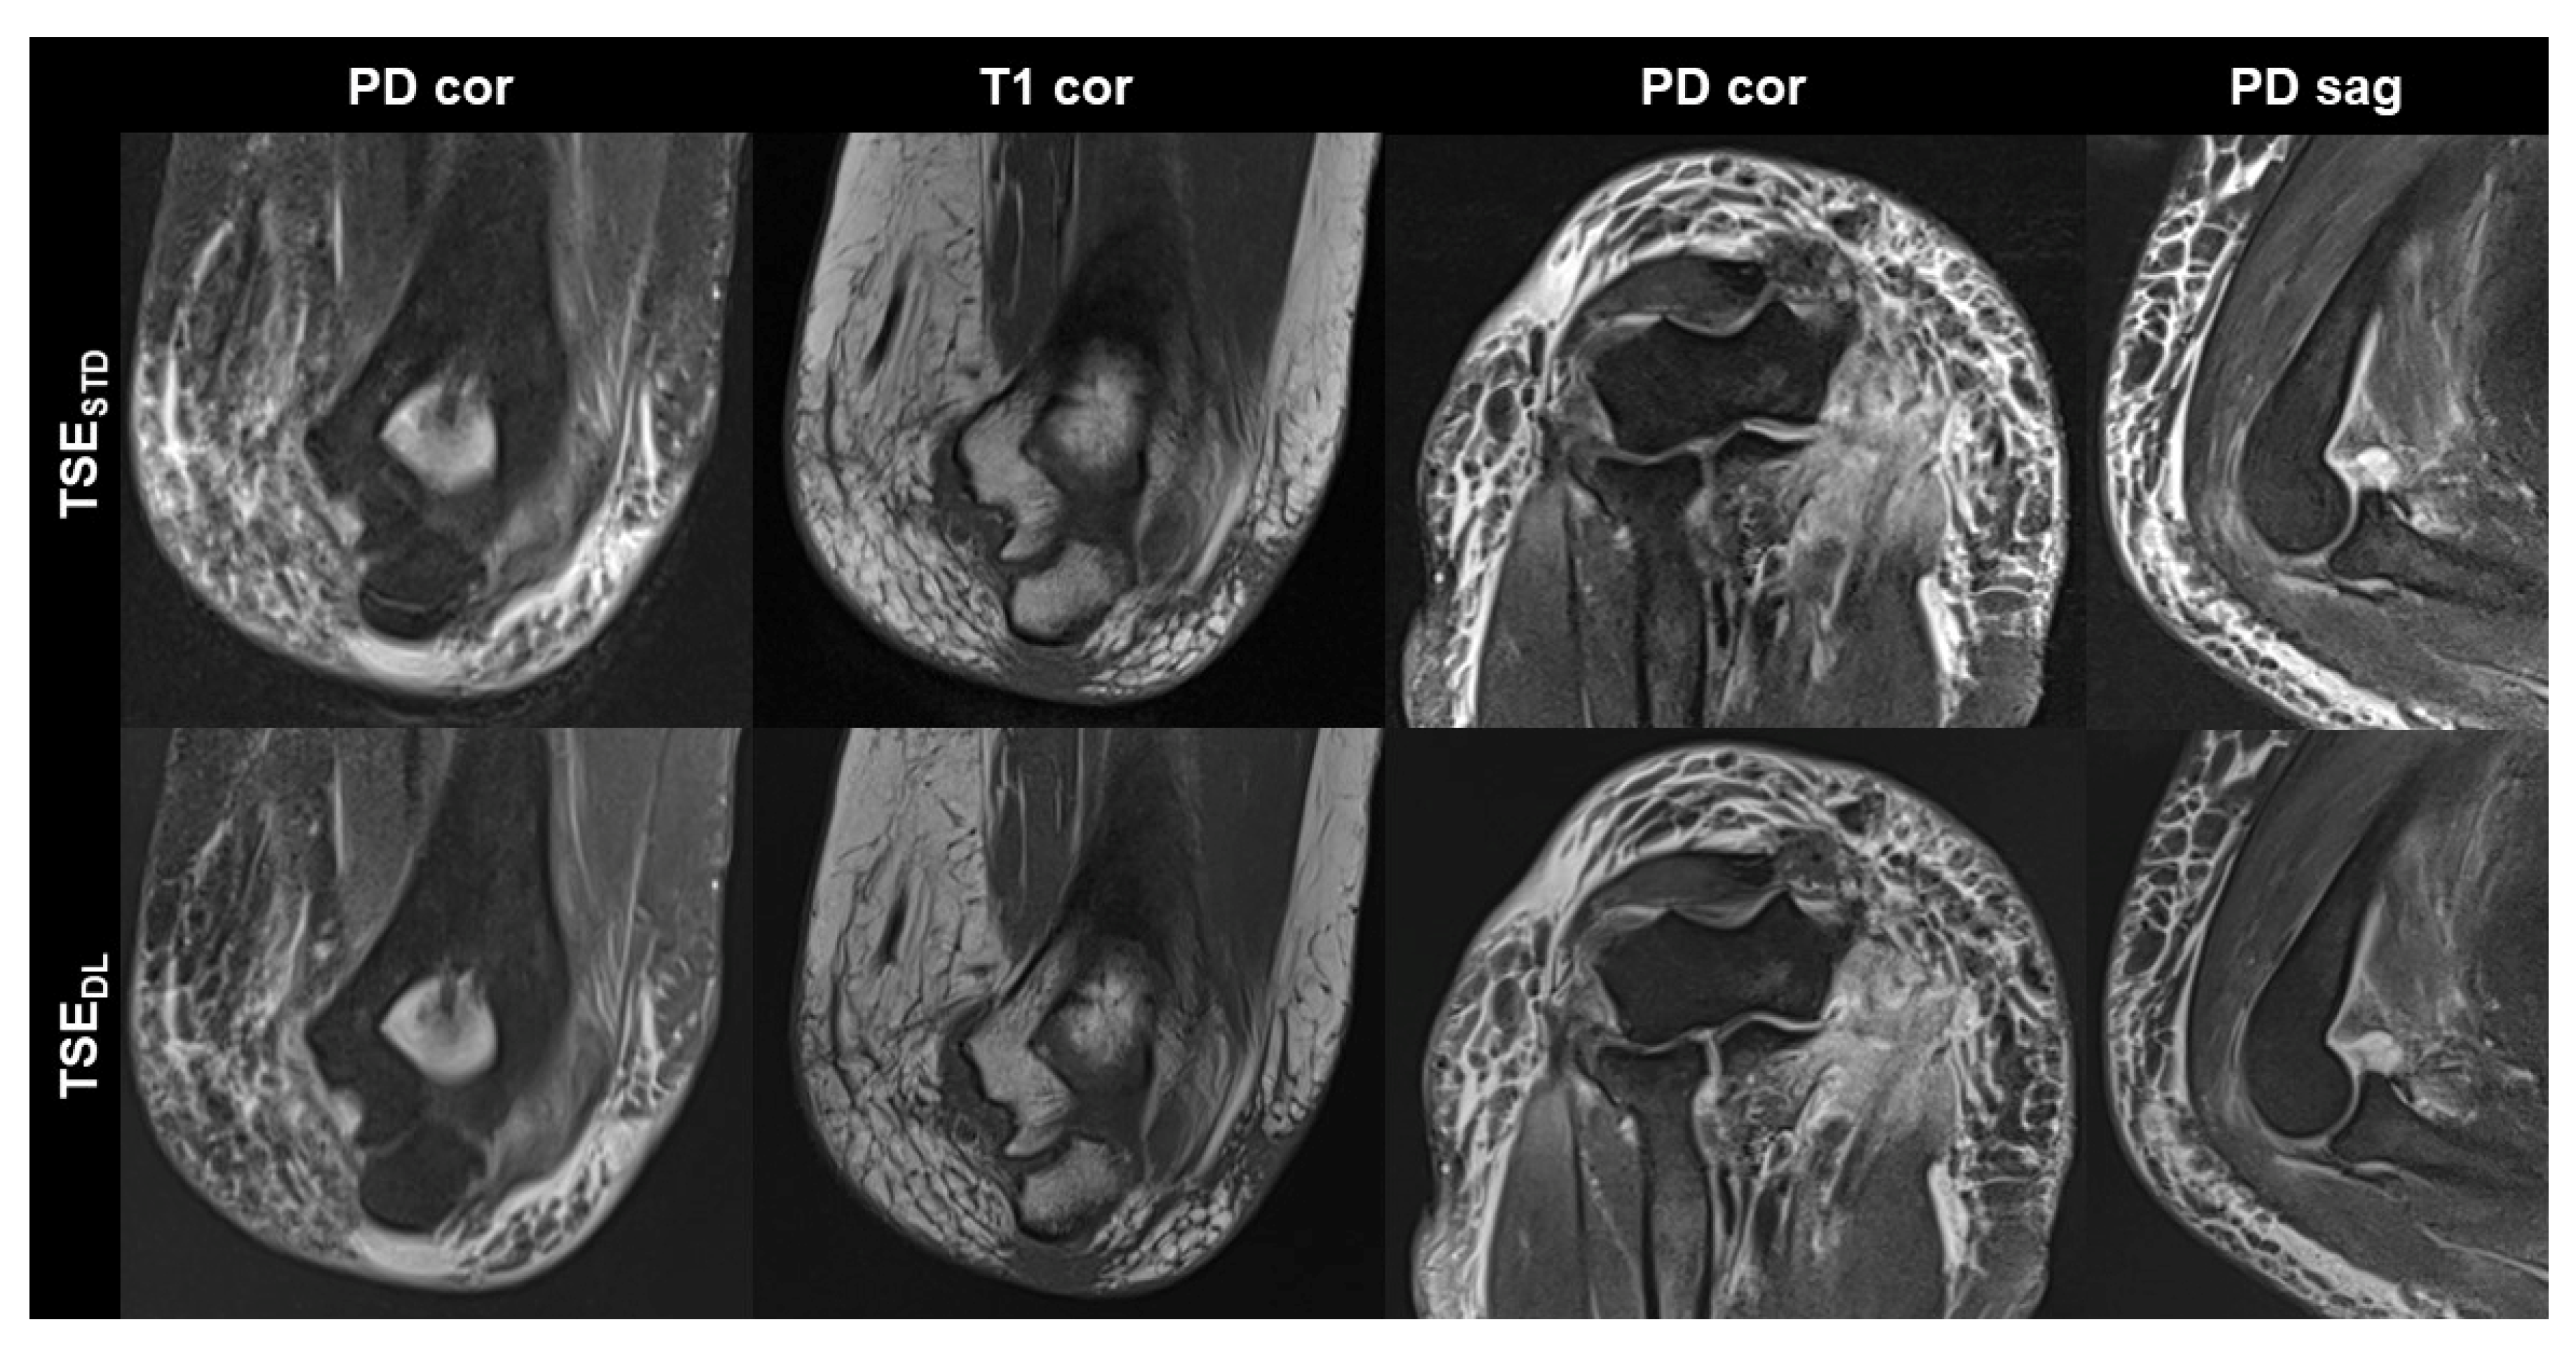

TSEDL was successfully performed in each of the 17 included participants (mean age 43 ± 16 (20–70), years, eight men). Seven exams were performed at 1.5 T and 10 exams at 3 T. TSEDL enabled a scan time reduction by more than 35% at 1.5 T (TSEDL 8:19 min vs. TSESTD 13:06 min) and by more than 55% at 3 T (TSEDL 6:48 min vs. TSESTD 15:15 min). Image examples with comparisons of TSESTD and TSEDL are displayed in Figure 1, Figure 2, Figure 3 and Figure 4.

Figure 4. Elbow MRI acquired at 1.5 T with the institution’s standard turbo spin echo (TSE) sequences (TSESTD, upper row) and deep learning reconstructed TSE sequences (TSEDL, lower row) in a 66-year-old female patient who had suffered an elbow dislocation. The patient could not extend the elbow for the examination. The images show an avulsion of the common flexor tendon with hemorrhage into the flexor muscles (PD cor and PD cor), a complete tear of the radial collateral ligament (PD cor, third column) and a dislocated annular ligament (PD sag). The fat-supressed PD-weighted TSEDL images show improved noise, while the DL-reconstructed coronal T1-weighted image shows very similar image quality compared to the standard image.